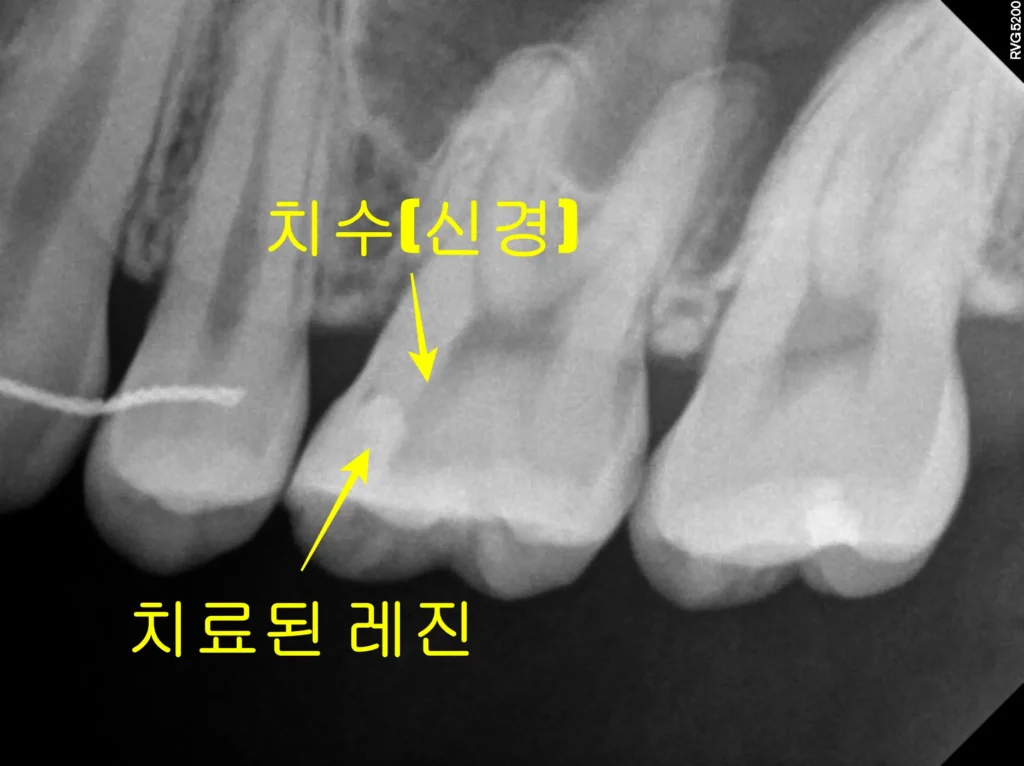

육안으로 볼 때는 치아가 깨끗해 보였습니다. 하지만 X-ray 촬영 결과는 달랐습니다. 기존에 치료된 레진 하방으로 깊은 충치가 관찰되었습니다. 신경관과 거의 닿아 있을 정도로 아주 깊은 상태였습니다. 충치가 깊어 신경과 가까울수록 레진 치료 시 접착에 매우 신경 써야 합니다. 접착이 완벽하지 않으면 치아와 레진 사이 경계면이 계속 자극을 받습니다.

시간이 지나면 신경이 예민해집니다. 결국 신경치료가 필요한 상태로 악화됩니다. 환자분은 치료 직후부터 6개월 이상 시림 증상을 겪으셨습니다. 진단 결과 해당 치아(#26번)는 비가역적 치수염(Pulpitis) 상태였습니다. 이미 신경이 회복 불가능한 상태라 신경치료를 결정했습니다.